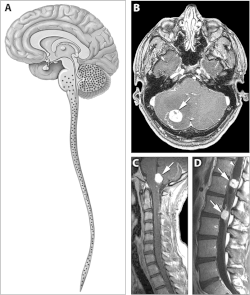

| Locations of the main types of cysts and tumors in Von Hippel–Lindau disease.[2] | |